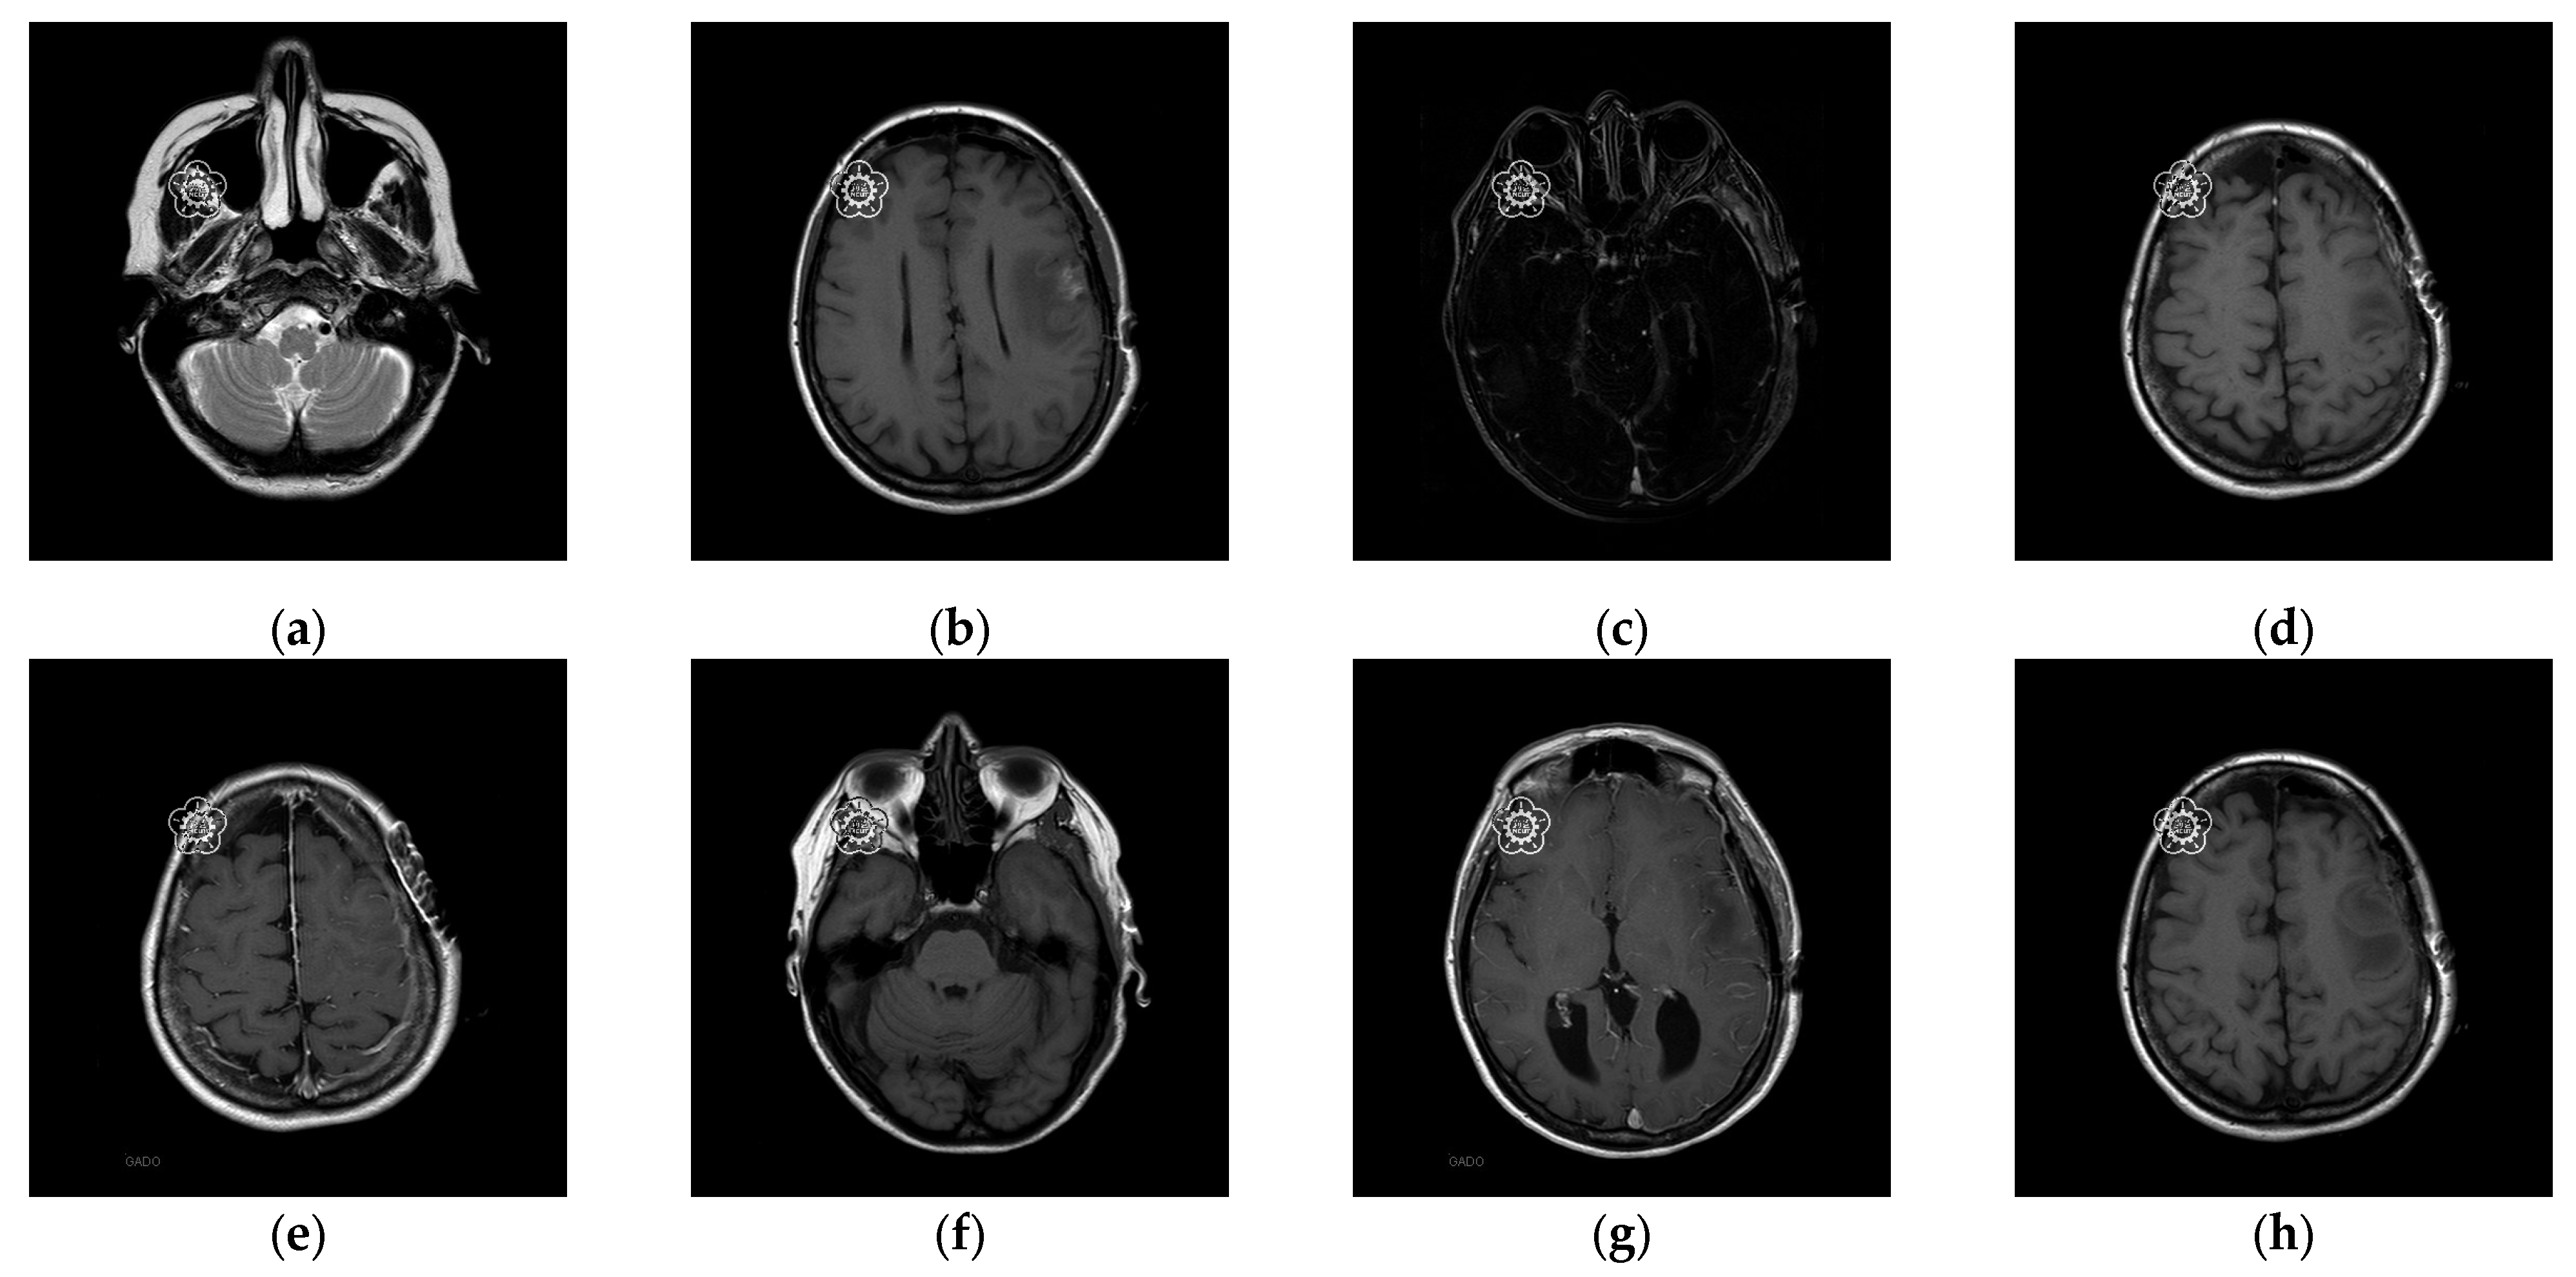

The experiments were conducted on two systems. The first system ran on Ubuntu 22.04, equipped with an Intel i7-9700KF CPU @ 3.60GHz (8 cores), an Nvidia GeForce RTX 3090 GPU, 32 GB of RAM, and Pytorch (https://pytorch.org/) for the experimentation. The second system, called the Type 1 device, is a notebook with an Intel(R) Core (TM) i7-10510U CPU @1.80 GHz 2.30 GHz, 16.0 GB RAM, 64-bit Windows operation system, and GPU MX 250. The third system, called the Type 2 device, is a notebook with an 11th Gen Intel(R) Core(TM) i5-11400H @ 2.70 GHz 2.69 GHz, 24.0 GB RAM, 64-bit Windows operation system, and GPU Nvidia GeForce 3060. The second system is a notebook that was released around 2019 or early 2020. The third system is also a notebook that was released in early 2021. The two systems were used to simulate resource-constrained environments. Different medical and test images were used as the test images to evaluate the performance of our proposed scheme and to make comparisons between our scheme and Qin et al.’s scheme [20]. In the first experiment, eight medical images, which are MRI scans of the brain, were randomly selected from the Osirix database [21] as test images and are presented in Figure 10 to demonstrate the performance of our proposed scheme in detail. In the second experiment, one hundred medical images, which are also MRI scans of the brain, were randomly selected from the Osirix database [21] to form Dataset 1 and Dataset 2, as shown in Figure 11, to prove the stable performance of our proposed scheme. In the third experiment, six general grayscale images, sized 512 × 512, demonstrated in Figure 12, were used to compare with those offered by Qin et al.’s scheme [20]. The logo depicted in Figure 13a was used as the watermark for the first and the second experiments and Figure 13b was used as the watermark for the third experiment.

To better align our VUF-MIWS with the practical needs of clinicians for authenticating medical image sources, we conducted a pilot interview at a regional hospital. In this interview, we defined the critical diagnostic reference area of a medical image as the ROI (Region of Interest) and divided it into nine sub-regions, as shown in Figure 14. We then asked seven doctors to indicate their two most preferred locations for visible watermarks. Based on the collected feedback, sub-region A received the highest number of votes (a total of nine), followed by sub-regions E and I (both receiving five votes). Therefore, sub-region A was selected as the watermark position for the first and second experiments. The resulting watermarked images for the first experiments are displayed in Figure 15.

Figure 11. Two datasets are used to test the stable performance of the proposed scheme. (ad) are Dataset 1, images of the pituitary gland taken from back to front. (eh) are Dataset 2, images of the pituitary gland taken from top to bottom.